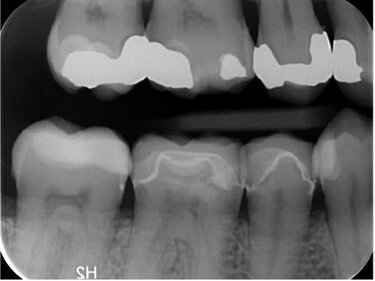

The plan was to place four indirect restorations, all done in a single visit. The first premolar and second molar were restored with milled inlays using IPS Tetric CAD. The second premolar and first molar were restored with full coverage restorations using IPS e.max CAD®.

Restorations designed using CEREC Primescan. A combination of full coverage and inlay restorations have been fabricated digitally.

Two e.max ceramic onlays and two tetric cad inlays. Resin cement was used to bond the restorations - immediate post-operative.

Restorations fabricated using CEREC Primescan, Primemill, and Ivoclar Vivadent IPS e.Max and Tetric CAD.